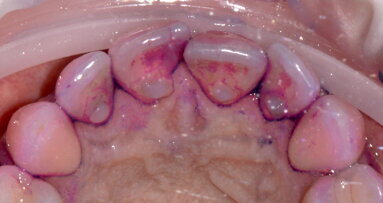

Una paziente affetta da amelogenesi imperfetta generalizzata (Figg. 1a, 1b) aveva richiesto in età adulta un trattamento estetico. La paziente ...